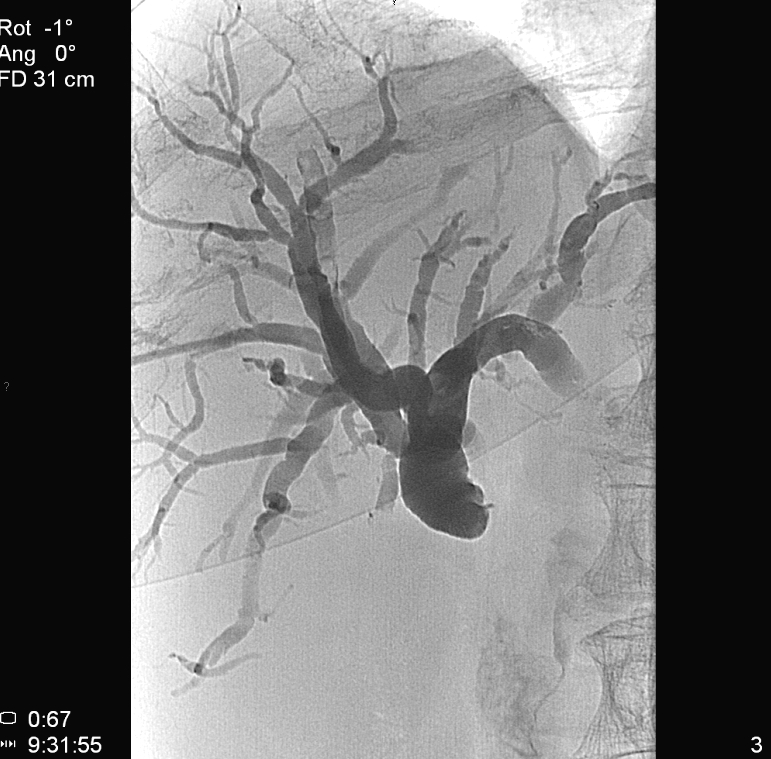

TAE (Transcatheter Arterial Embolization) and TACE (Transcatheter Arterial ChemoEmbolization) are methods with which the supplying artery/arteries of the tumor are selectively approached through the branches of the hepatic artery. When the catheter is in position the tumor branches are injected with a special, oily contrast material, Lipiodol (TAE). The injected material is used as an embolization material (figure 18.), other chemotherapeutical drugs (5-Fluoro-Uracil, Epirubicin, Cisplatin, Mytomicin-C) can also be used (TACE) (figure 19.).

Image

Figure 18. – Lipiodol uptake in HCC, selective catherarization, injection of 10 ml Lipiodol (DSA)

Figure 19. – TACE, CT control (2 weeks after treatment)

Compared to systemic chemotherapy, with these methods 10 or even 100 times greater drug concentrations can be delivered to the tumor tissue. Moreover, due to the effects of Lipiodol, the drug effects persist longer, while normal liver parenchyma will wash out the chemicals faster leaving little or no harm.

This can be successfully combined with the other percutaneous methods, especially during the treatment of multiplex primary and secondary tumors.